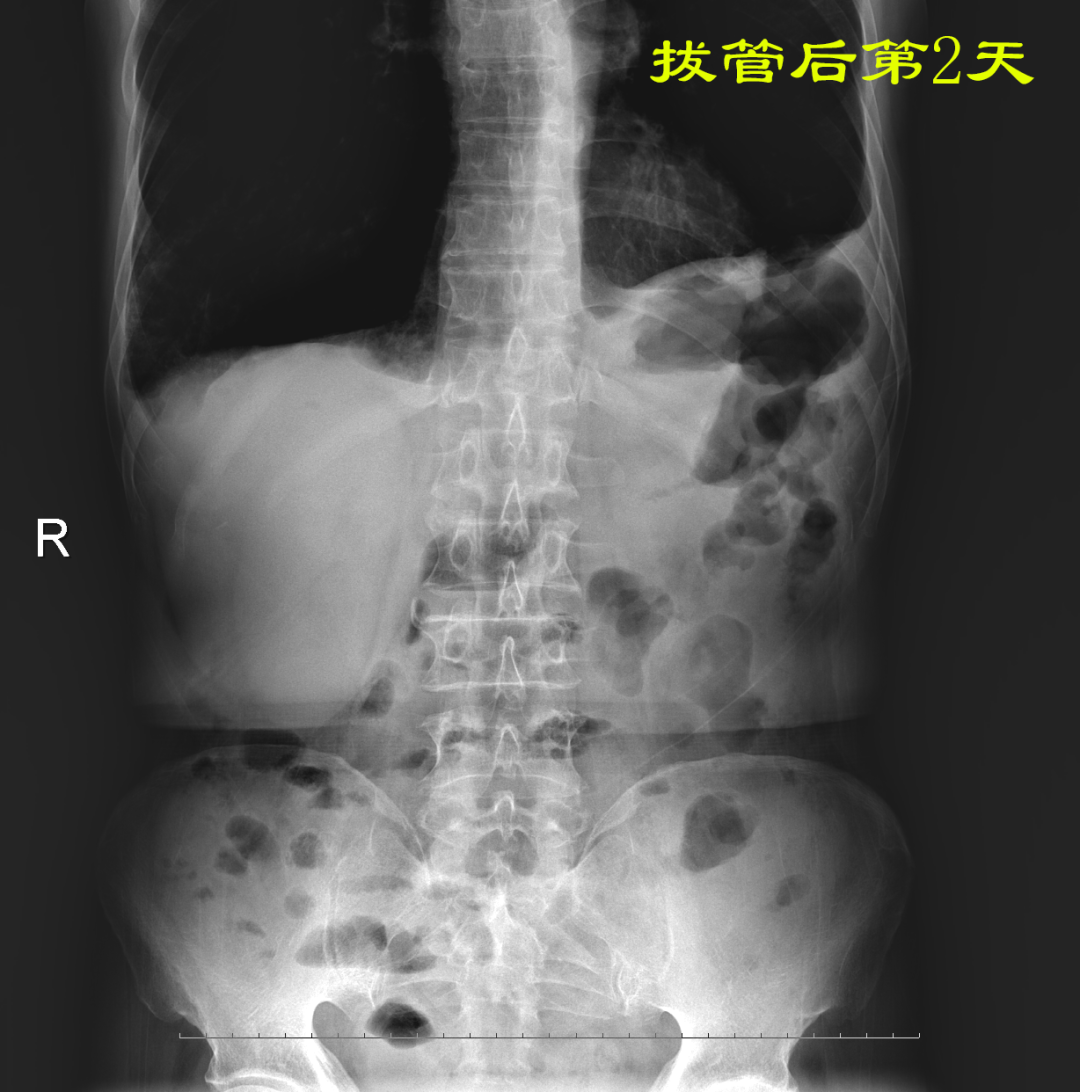

病例:患者男性,74岁,因“腹痛、腹胀伴呕吐、肛门停止排气排便20小时”于2021年7月24日入住我院普外科。患者1月前因回肠穿孔于我院普外科手术治疗,入院后明确诊断为术后粘连性小肠梗阻,经胃管引流等保守治疗无好转。因患者有严重心肺疾患,再次手术风险较大,并且术后再发粘连性肠梗阻的可能性也很大。经过与患者家属沟通后,最后决定采用胃镜引导下置入经鼻插入型肠梗阻导管技术来治疗肠梗阻。由我院消化内科副主任医师杨开余完成操作,耗时大约40分钟,患者术后第5天开始排气排便,腹痛、腹胀症状迅速消失,术后第7天拔除肠梗阻导管,恢复饮食。拔管至今已10天,患者已出院。随访患者无腹痛、腹胀,排便正常。